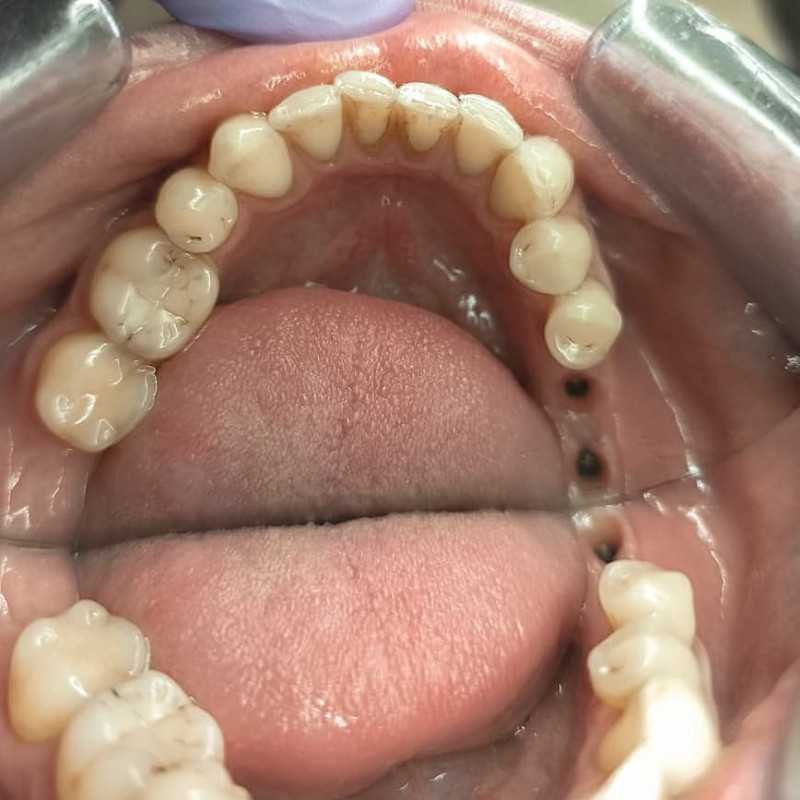

Жалобы: на отсутствие зубов, неудовлетворительную эстетику зубных рядов, невозможность жевать, подвижность зубов. Что сделано: удаление зубов на в/ч и н/ч, установка имплантатов Bredent Sky (верхняя челюсть 6 импл, нижняя 4 импл) и одномоментное протезирование акриловыми протезами с опорой на имплантаты по протоколу Fast & Fixed (зубы за один день). Через 10 месяцев проведена работа по замене протезов на постоянные металлокерамические. Что получил пациент: красивую улыбку, возможность нормально питаться с первого дня после операции.